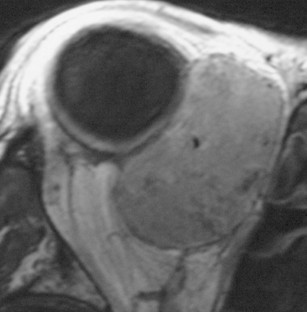

Eine 53-jährige Patientin stellte sich mit einer seit 18 Monaten bestehenden tastbaren Raumforderung der rechten medialen Orbita vor. Das linke Auge war im Kindesalter wegen einer perforierenden Verletzung enukleiert worden. Eine auswärts durchgeführte orbitale Biopsie hatte bis auf unspezifische Entzündungszeichen keine klärende Diagnose erbracht. Eine auswärts durchgeführte systemische Therapie mit Kortikosteroiden war ohne Erfolg. Eine zweite orbitale Biopsie wurde in unserer Klinik durchgeführt und zeigte einen solitären fibrösen Tumor (SFT) der Orbita. Eine mediale Orbitotomie mit Tumorexzision erfolgte und die histologische Untersuchung des exzidierten Tumors ergab einen SFT der Orbita mit fokaler sarkomatöser Transformation. Die Patientin stellte sich 3 Jahre später mit einer neuen Raumforderung in einer MRT-Kontrolluntersuchung vor. Bei hochgradigem Verdacht auf ein Rezidiv wurde eine Orbitotomie mit Exzision der Raumforderung durchgeführt. Die histologische Untersuchung zeigte einen rezidivierenden SFT der Orbita mit sarkomatöser Transformation in seiner gesamten Ausdehnung. Anschließend wurde eine Radiotherapie mit einer Gesamtdosis von 59,4 Gy durchgeführt. Die Patientin war tumorfrei bei der letzten Kontrolluntersuchung 3 Jahre später.

A 53-year-old female patient presented with a palpable mass in the right medial orbit which had been present for 18 months. The left eye had been enucleated in childhood due to a perforating injury. An orbital biopsy performed ex domo showed unspecific inflammatory tissue but no definite diagnosis was made and systemic therapy with corticosteroids was unsuccessful. A second orbital biopsy was performed in our clinic and revealed a solitary fibrous tumor (SFT) of the orbit. Medial orbitotomy with tumor excision followed and the histological examination of the excised tumor established the diagnosis of SFT of the orbit with focal sarcomatous transformation. The patient presented 3 years later with a new orbital mass in a control MRI examination. Relapse was suspected and orbitotomy with excision of the mass was performed. The histological examination revealed a relapse of the SFT with sarcomatous transformation in the whole extent of the tumor. Radiotherapy with a dosis of 59.4 Gy was subsequently performed. The patient remained tumor-free in the most recent control examination 3 years later.

Abb. 2